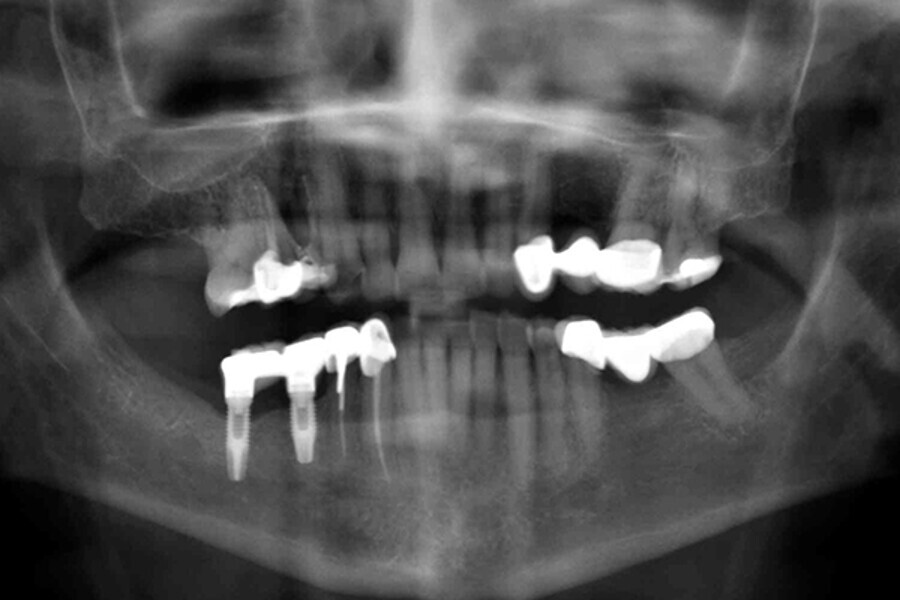

Figs. 9. Colocación de 2 implantes post-extracción en posiciones del 43 y 44 y control radiográfico post-extracción.

Figs. 10. Colocación de 2 implantes post-extracción en posiciones del 43 y 44 y control radiográfico post-extracción.